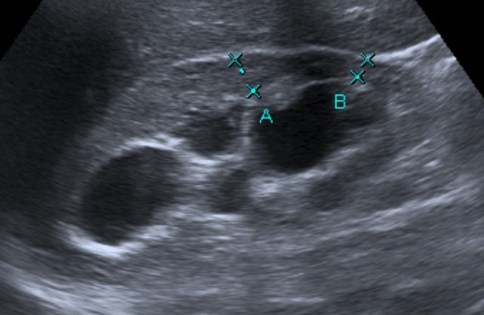

3- Ecografía:

Tiene varias ventajas, es una prueba con bajo riesgo, barata, disponible, sin radiación y no requiere el uso de material de contraste. Suele ser la primera prueba que se realiza para valorar una pielonefritis. Sin embargo, en adultos es una herramienta que no caracteriza bien la infección renal, por ello, la mayoría de pacientes tienen un resultado negativo, pudiendo demostrar signos en tan solo un 24% de casos y por ello que decimos que infraestima la gravedad de la pielonefritis. Con el uso de material de contraste ecográfico (microburbujas) la S y E de la ecografría es mayor, sin embargo, son necesarios más estudios al respecto.

Cuando se dan hallazgos, lo más frecuente es observar un aumento del tamaño renal, hidronefrosis, litiasis o alteraciones de la vía urinaria. Otros signos que a veces pueden observarse incluyen colecciones, pérdida de definición del seno renal por el edema, focos hipoecoicos por edema o colecciones, focos hiperecoicos de hemorragía, pérdida de diferenciación córtico-medular, áreas hipoperfundidas con baja señal Power Doppler. Las calcificaciones pueden ser difíciles de distinguir del gas. Puede ser limitada para detectar focos de infección perirrenal o abscesos pequeños en infecciones en fases precoces.